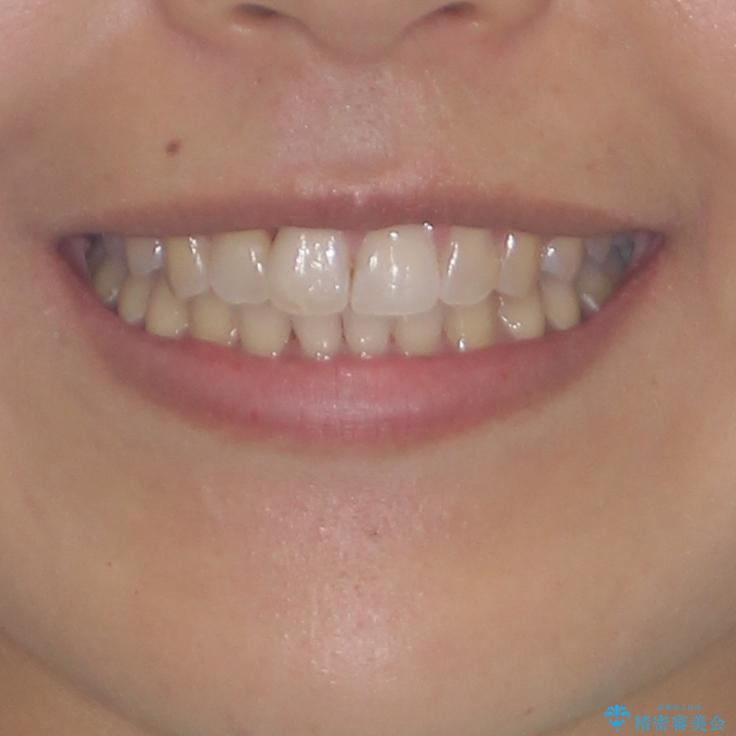

前歯のデコボコをインビザラインでスッキリと仕上げる

- 上下前歯のデコボコと奥歯の銀歯を気にして来院された患者様です。

口元をインビザラインにより歯列を整え、その後に失活している奥歯をオールセラミッククラウンにて補綴治療することとしました。

長時間のマウスピース装着に協力いただき、自然な口元に仕上げることができました。

気になっていた銀歯もオールセラミッククラウンで本物の歯のようになり、患者様には大変満足していただきました。